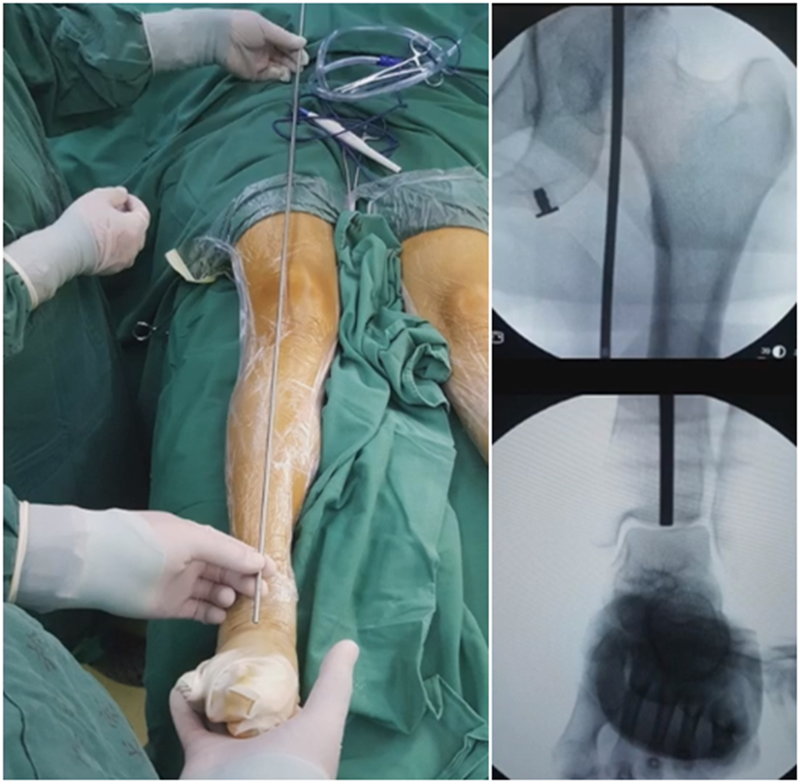

1、体位

医生站于患肢对侧,CB机置于同侧,以便于术中实时监测影像。

3、核实力线

术前推荐用力线杆核实力线,通常在术前计划时,需要做下肢全长片,但是有些医院的下肢全长片为拼接而来,可能会存在拼接误差,继而影响术前计划的准确性,因此推荐术前再次使用力线杆评估力线,以保证与术前计划一致。

合页点和截骨线已确定好,按照术前计划打入导针,测量截骨深度。

水平截骨时,同样放肢体中立位,后侧放一把骨撬保护后方重要结构。

然后核实力线,如力线位置良好,就可以采用内固定的方式将位置维持好。